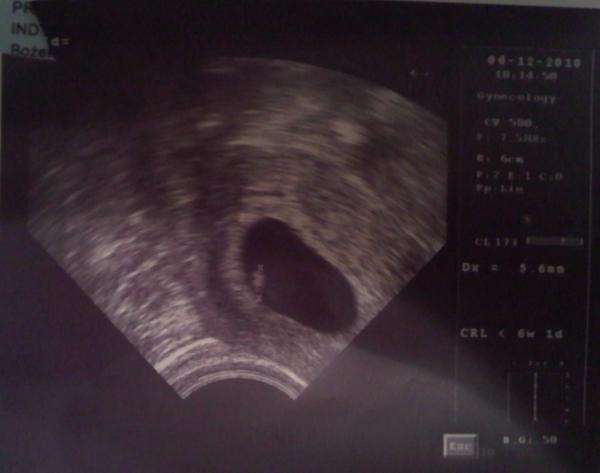

Dodane przez: zeddez Opis zdjęcia: Nasze Bambino-pierwsze zdjęcie Podziel się ze znajomymi! Skopiuj i prześlij poniższy link: URL: |

Mama Weronisi 2010.12.07 22:14

Gratulacje!